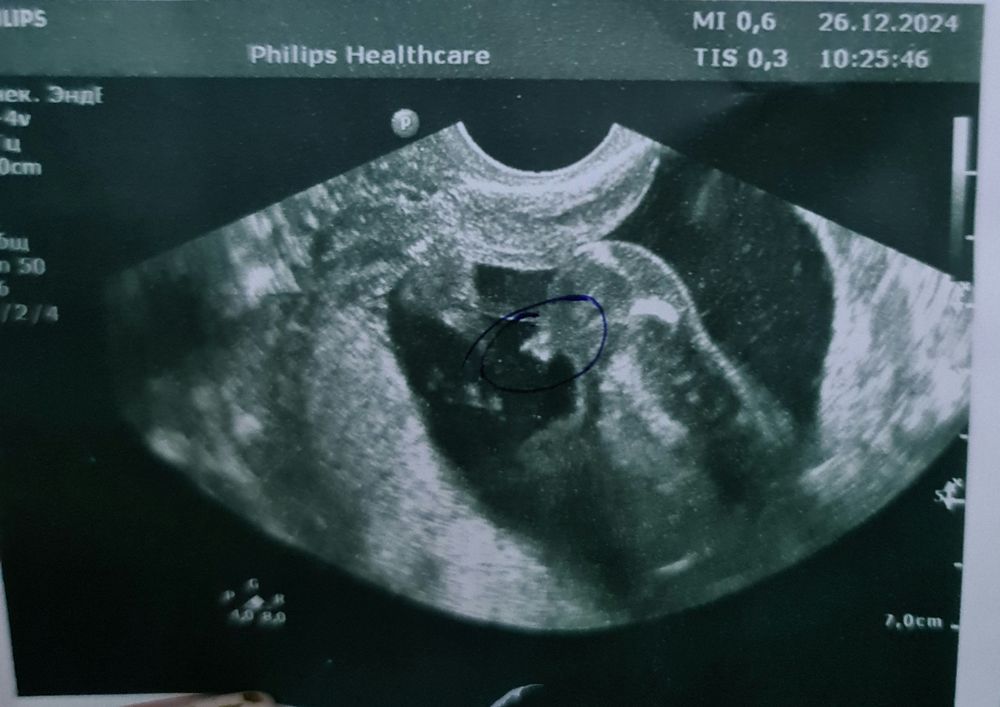

Мальчик?

А, все вижу У вас 18 Значит пацан по любому 😄

Альбина , завтра будет ровно 18 недель)

А недель то сколько? Если первый скрининг, то дождитесь 16-17 недель хотя бы, тогда точно скажут Мне на первом мальчика говорили, прям показывали где что, в итоге второй скрининг девочка

Это мальчик? Домашний фетальный доплер?